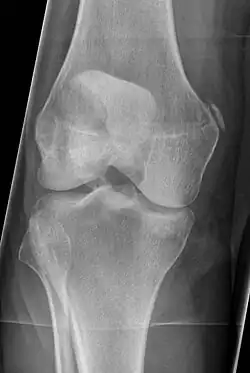

Pellegrini-Stieda syndrome. Also visible is a fracture of the patella. |

Pellegrini–Stieda syndrome (also called Stieda disease and Köhler–Pellegrini–Stieda disease) is the ossification of the superior part of the medial collateral ligament of the knee. It is a common incidental finding on knee radiographs. It is named for the Italian surgeon A. Pellegrini (b. 1877) and the German surgeon A. Stieda (1869–1945).[1] While the eponym refers to Pellegrini and Stieda, the condition was first discovered by Köhler in 1903, before any namesakes. Pellegrini-Stieda combines the aforementioned radiographic findings and concomitant medial knee joint pain or restricted range of motion.[2]

Diagnosis is typically made on radiographs demonstrating the Pellegrini-Stieda syndrome sign accompanied by pain or restriction of range-of-motion of the knee joint.[2] Pellegrini-Stieda syndrome sign is typically described by a longitudinally linear opacity, which is a process that is describes characteristic of calcification in the soft tissue located medial to the medial femoral condyle.[2] This calcification seen on imaging represents the ossification of the medial collateral ligament, which typically does not develop until approximately three weeks after the initial injury.[2]It is important to note to distinguish this radiographic finding from that of a medial femoral condyle avulsion fracture, which is an injury in which a pulling force of a tendon or ligament fractures away a piece of the bone from its attachment site.[2]